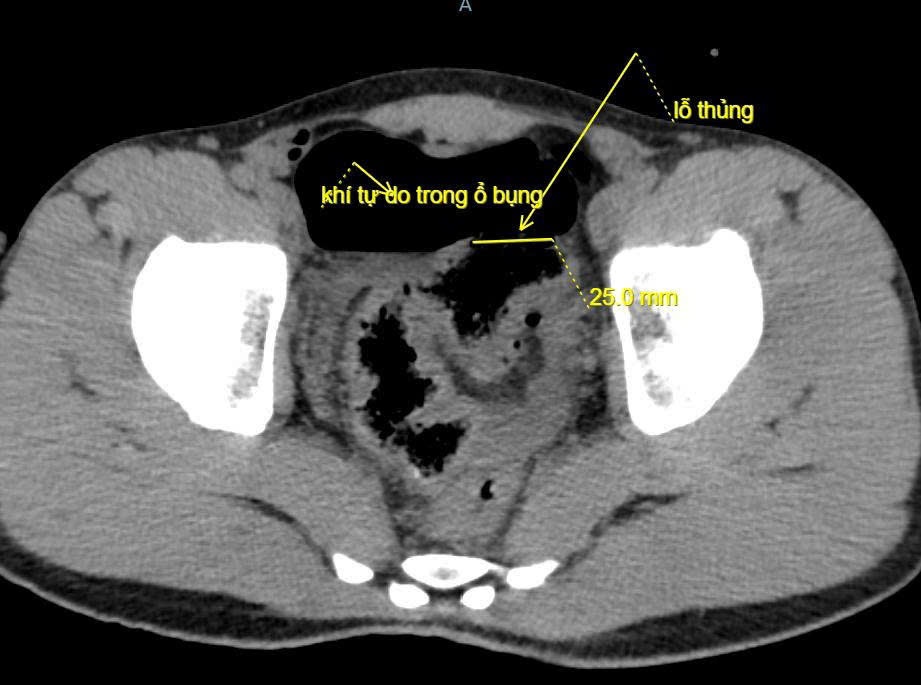

Bệnh nhân là nam giới, nhập viện trong tình trạng đau bụng dữ dội, bụng chướng căng, khó thở và mệt lả. Khai thác bệnh sử ghi nhận trước đó, bệnh nhân bị bạn trêu đùa và dùng vòi xịt rửa ôtô (vòi áp lực cao) để xịt vào hậu môn. Kết quả chụp X-quang và CT scan ổ bụng cho thấy nhiều khí tự do trong ổ bụng, nghi ngờ thủng tạng rỗng. Ngay sau khi tiếp nhận, bệnh nhân được chỉ định mổ cấp cứu.

Ê-kíp phẫu thuật mổ mở bụng thăm dò, phát hiện ổ bụng có khoảng 100 ml máu và dịch bẩn. Đại tràng sigma có đoạn tổn thương dài 5 cm, lỗ thủng khoảng 2 cm, xung quanh dập nát. Bệnh nhân được cắt lọc lỗ thủng, khâu đoạn đại tràng tổn thương, làm sạch ổ bụng và đặt dẫn lưu.

Ảnh chụp cắt lớp vi tính ổ bụng bệnh nhân. Ảnh: BVCC.